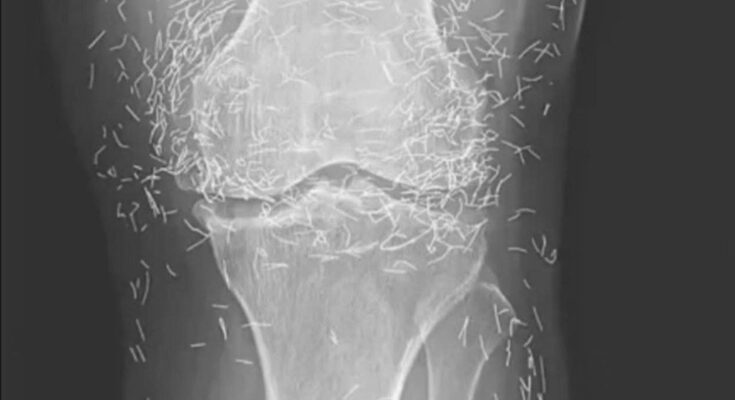

Acupuncture, an alternative treatment with a history spanning centuries, entails the insertion of needles into specific points on the body to alleviate pain or address various health issues. In this particular instance, the needles—likely crafted from gold—were deliberately left in her knees to provide ongoing stimulation.

However, the practice of leaving needles within the body carries inherent risks.

“The presence of foreign objects within the body can result in inflammation, abscesses, and infections,” stated Dr. Ali Guermazi, a radiology professor at Boston University who was not associated with the case.

He further cautioned that needles left embedded can interfere with X-ray interpretations. “The needles may obscure certain anatomical structures,” Guermazi remarked in 2013.

Moreover, the human body does not always respond favorably to foreign entities, and such reactions may be classified as foreign body reactions or chronic inflammatory responses.

“The human body instinctively attempts to expel the foreign object,” Guermazi elaborated. “This process begins with a defensive mechanism, such as inflammation and the formation of fibrous tissue around the object.”

Even more troubling, needles that remain in the body can pose risks for future medical imaging. “The patient cannot undergo an MRI because needles left in the body might shift and injure an artery,” Guermazi noted.